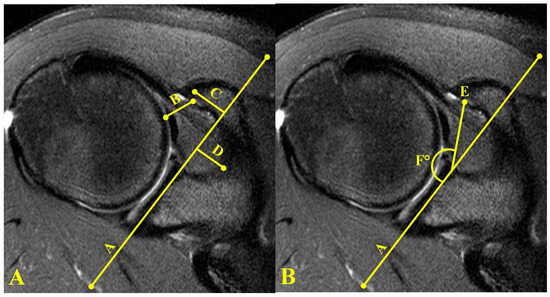

- Giaroli, E.; Major, N.; Lemley, D.; Lee, J. Coracohumeral interval imaging in subcoracoid impingement syndrome on MRI. AJR Am. J. Roentgenol. 2006, 186, 242–246. [Google Scholar] [CrossRef]

- Tan, V.; Moore, R.; Omarini, L.; Kneeland, J.; Williams, G.; Iannotti, J. Magnetic resonance imaging analysis of coracoid morphology and its relation to rotator cuff tears. Am. J. Orthop. (Belle Mead NJ) 2002, 31, 329–333. [Google Scholar]

- Richards, D.; Burkhart, S.; Campbell, S. Relation between narrowed coracohumeral distance and subscapularis tears. Arthroscopy 2005, 21, 1223–1228. [Google Scholar] [CrossRef] [PubMed]

- Asal, N.; Şahan, M.H. Radiological Variabilities in Subcoracoid Impingement: Coracoid Morphology, Coracohumeral Distance, Coracoglenoid Angle, and Coracohumeral Angle. Med. Sci. Monit. 2018, 24, 8678–8684. [Google Scholar] [CrossRef]